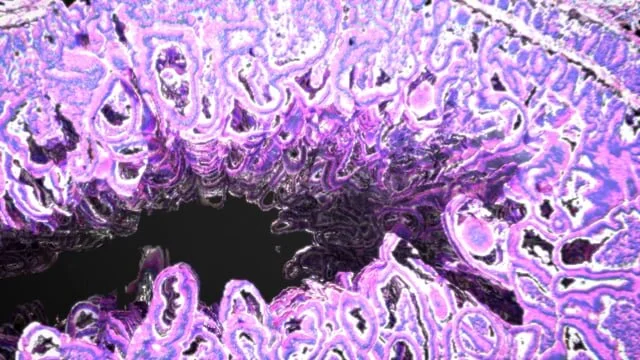

Tissue Reconstruction - Beauty Renders

Tissue Reconstruction - Workflow